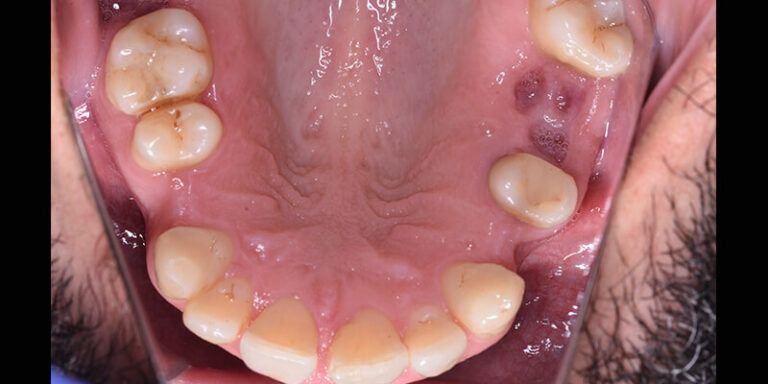

También se le explica la necesidad de una fase ortodóncica previa a la reposición protésica de las piezas ausentes 14,24,26 y 46, cuyo objetivo es la alineación del sector anterior superior y la intrusión del mismo, especialmente del 23 y el cierre de los diastemas presentes, centrando la línea media y mejorando los espacios para la colocación de los respectivos implantes y sus correspondientes coronas.

Se dieron las instrucciones para alinear y nivelar los seis dientes anteriores superiores, cerrando los espacios hacia mesial y mejorando la sobremordida con intrusión de los incisivos y especialmente del 23 que estaba más extruido.

El stripping en incisivos laterales superiores e incisivos inferiores no debía ser mayor a 0.3mm por lado.